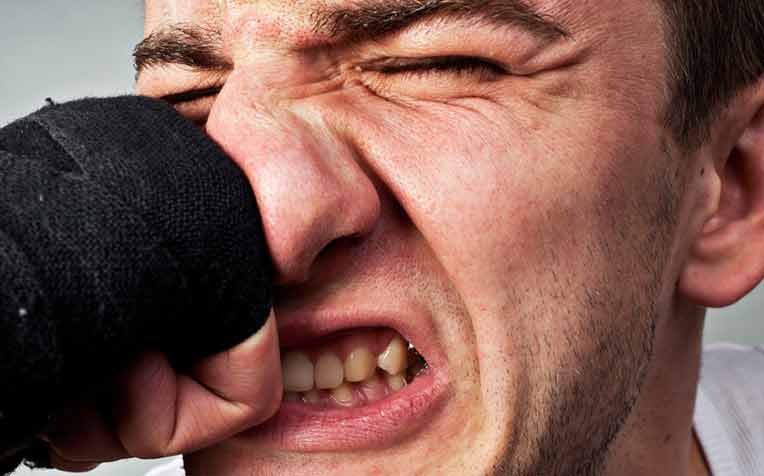

huanluyenantoan.edu.vn12+ Puñetazo Dado En La Nariz O Cara - AlcideJulia

huanluyenantoan.edu.vn12+ Puñetazo Dado En La Nariz O Cara - AlcideJulia

alcidejulia.blogspot.comFotos De Nariz Rota - Banco De Fotos E Imágenes De Stock - IStock

alcidejulia.blogspot.comFotos De Nariz Rota - Banco De Fotos E Imágenes De Stock - IStock